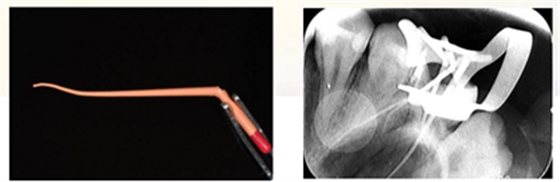

2、使用组织排开橡皮障夹(#B-1)上橡皮障,障布边缘翻转,隔离牙龈,封闭患牙。

3、去净腐质后,剩余健康牙体组织位于龈下,考虑行龈壁提升,因需使用成型片,拆除橡皮障。

4、使用成型片隔离牙龈,保证边缘密合不渗漏,SDR树脂龈壁提升。